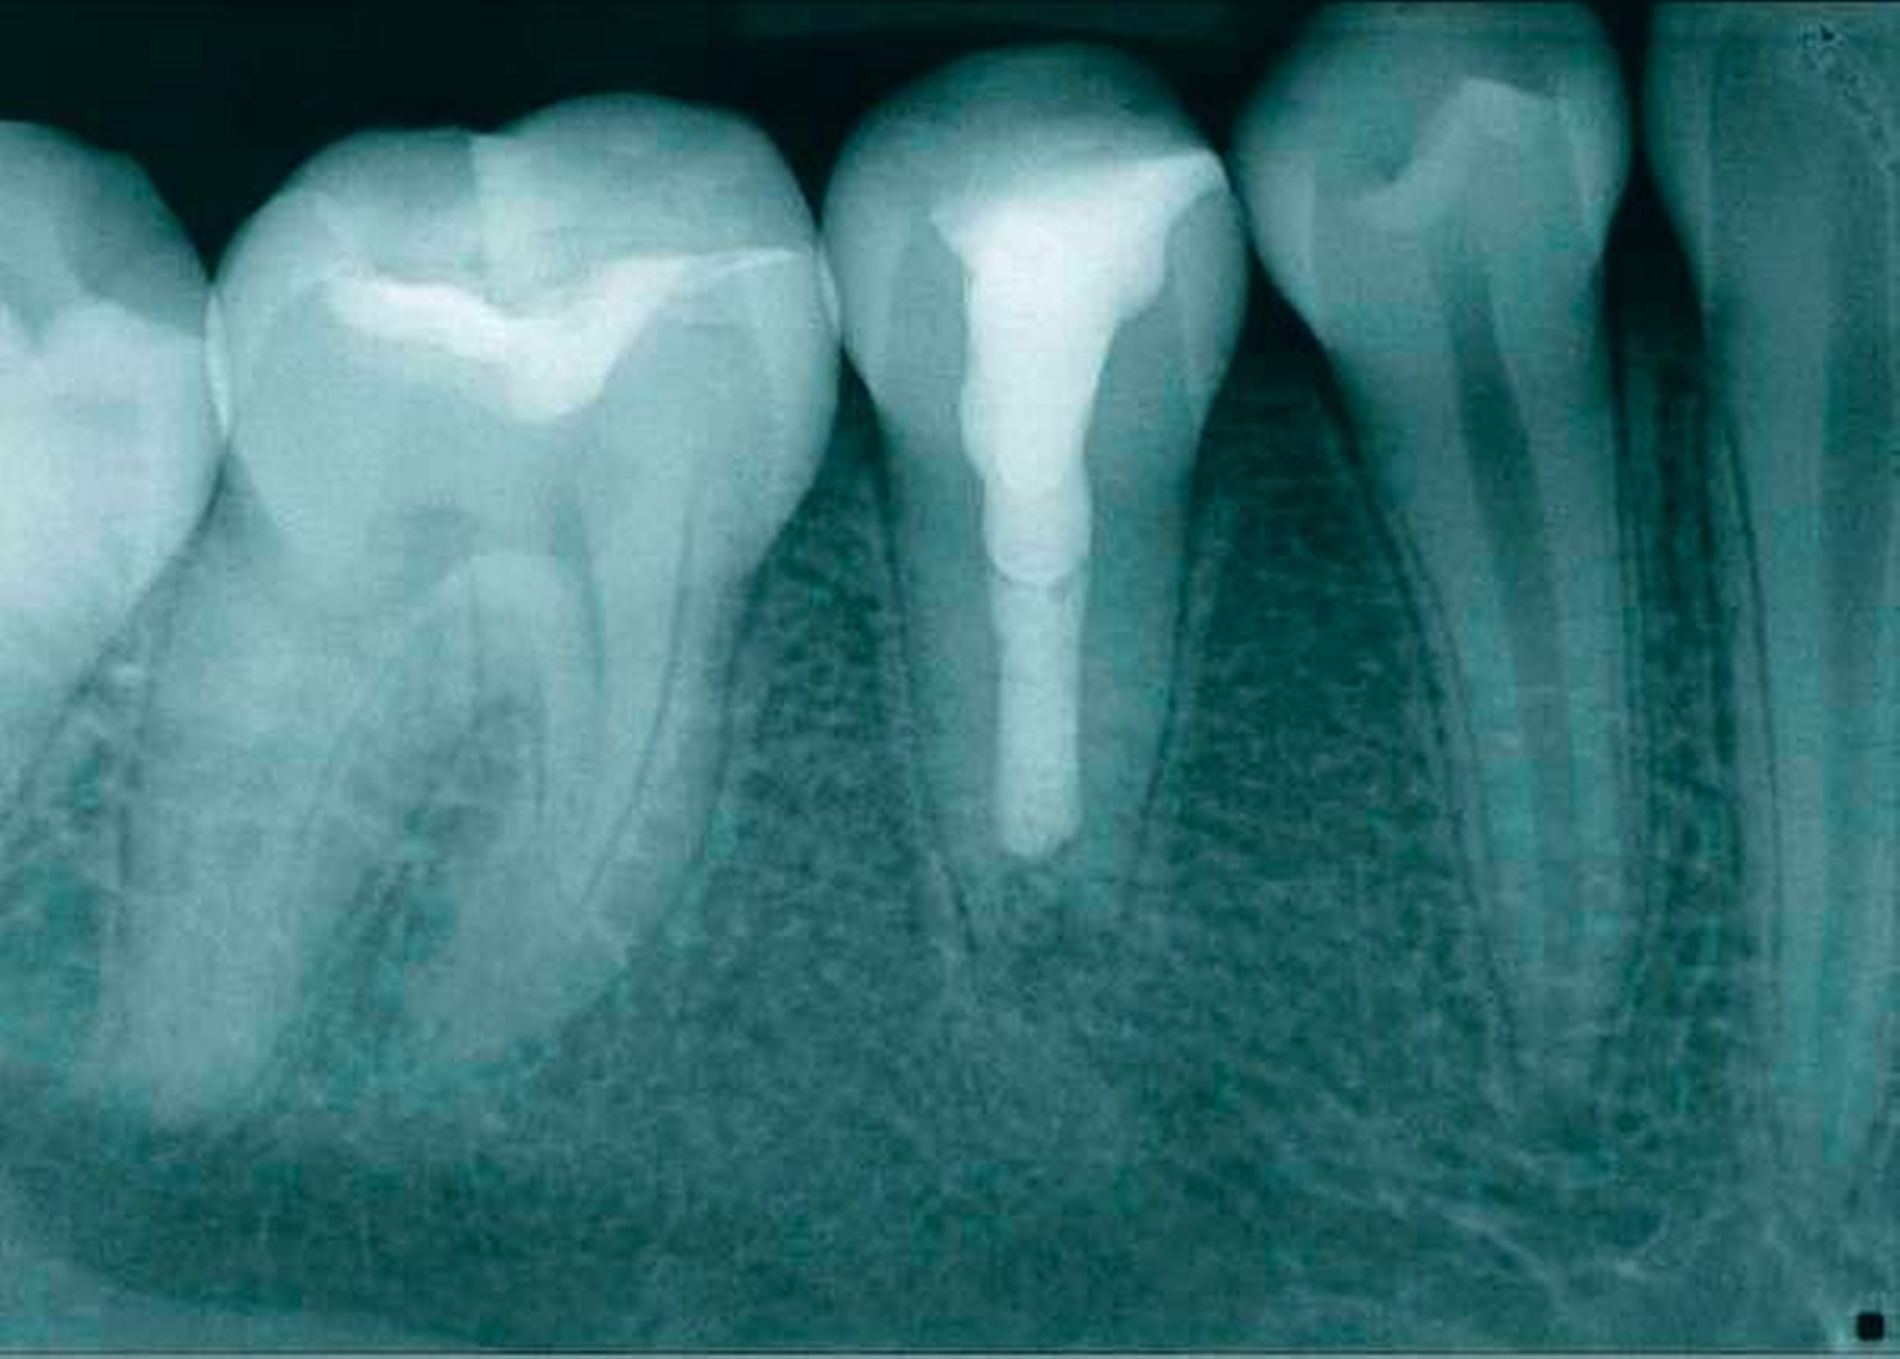

Die zweite Therapiesitzung folgte eine Woche später. Der Fistelgang war bereits ausgeheilt. Nach Spülung mit NaOCl 5 % und EDTA 17 % sowie der Schallaktivierung mittels EDDY (VDW, München) erfolgte die Trocknung des Zahnes. Im Anschluss wurde ein apikaler Verschluss mit weißem ProRoot MTA (Dentsply Sirona, York, PA, USA) appliziert (Abbildung 7). Der Plug wurde auf eine Länge von 15 mm eingebracht – genau der Punkt, ab dem die Patienten das Sondieren wieder gespürt hat. Zur Kontrolle des Plugs erfolgte eine Kontrollaufnahme vor definitivem Verschluss (Abbildung 8).